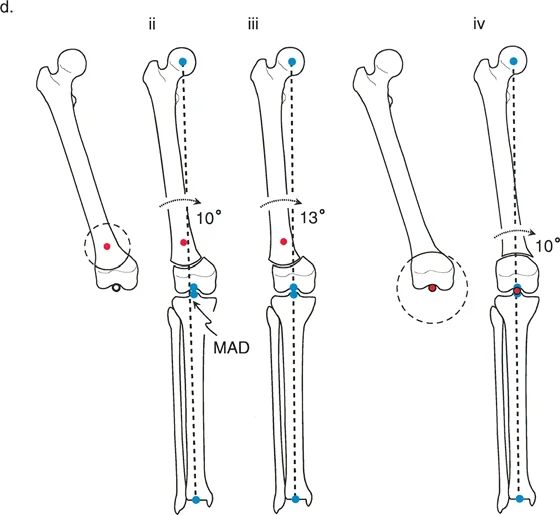

Osteotomy Rule Two Angulation with Translation

The Geometric Definition

When the ACA passes through the CORA, but the osteotomy line is made at a different level (either proximal or distal to the CORA).

The Biomechanical Result

The mechanical axis and joint orientation angles are perfectly restored. However, because the bone cut is made at a distance from the hinge point, the bone segments will mathematically translate relative to one another. This creates a visible "bump" or step-off in the anatomic axis. While the bone looks jagged on an x-ray, the load-bearing mechanical axis is flawless.

Clinical Application

Rule Two is frequently used for juxta-articular deformities. For example, if a patient has a severe distal femoral valgus deformity, the CORA may be located inside the knee joint. A surgeon cannot perform an osteotomy through the articular cartilage. Therefore, the surgeon must place the ACA at the joint (the true CORA) but perform the actual bone cut (osteotomy) safely in the metaphysis.

The resulting translation is not an error; it is a necessary and mathematically sound compromise to achieve a straight mechanical axis while cutting the bone in a biologically safe zone.

Osteotomy Rule Three Secondary Deformity

The Geometric Definition

When the osteotomy line and the ACA are both placed at a level different from the CORA.

The Biomechanical Result

A secondary translational deformity is created. While the angular deformity may appear to be corrected, the mechanical axis will not be fully restored. The proximal and distal mechanical axes will be parallel but not collinear, resulting in residual Mechanical Axis Deviation (MAD).

Clinical Application

In most cases, Rule Three represents an unintended surgical error. If a surgeon ignores the CORA and simply cuts the bone where it is most convenient, hiving it at the cut site, they will create a "golf club" deformity. The joint may be parallel to the floor, but the mechanical axis will be shifted, leading to rapid joint degeneration.

However, Rule Three can be used intentionally by master surgeons to correct pre-existing translational deformities. If a bone has a pre-existing translation, applying Rule Three can create an equal and opposite translation, effectively realigning the mechanical axis.

Juxta Articular Deformities

Deformities located very close to the joint line present a unique challenge. The CORA is often located within the epiphysis or the joint space itself.

- Surgical Pearl You cannot cut through the CORA in these cases. You must utilize Paley's Rule 2. Place your hinge (ACA) at the joint line (the CORA), and perform your osteotomy in the metaphyseal bone.

- Managing Translation Be prepared for the resulting translation. When using a plate for fixation, you may need to use a specialized offset plate or manually contour the plate to accommodate the step-off. If using an intramedullary nail, blocking screws (Poller screws) are essential to guide the nail and maintain the translation without allowing the bone to slide back into deformity.